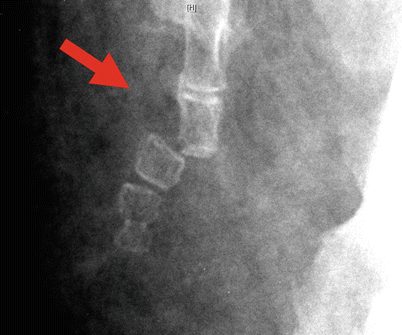

- อุบัติเหตุหกล้มก้นกระแทกพื้น เป็นสาเหตุที่พบได้บ่อยที่สุด เพราะในคนรูปร่างปกติ (ไม่อ้วนมาก) กระดูกก้นกบจะอยู่ชิดกับผิวหนังบริเวณก้น เวลาที่มีอุบัติเหตุหกล้มก้นกระแทกพื้น กระดูกก้นกบจึงมักจะกระแทกกับพื้นโดยตรง ทำให้เกิดอาการกระดูกก้นกบอักเสบ กระดูกก้นกบร้าว และกระดูกก้นกบหักได้ โดยการวินิจฉัยจำเป็นต้องมีการทำ X-ray เพื่อยืนยันสาเหตุของอาการเจ็บก้นกบ ที่คิดว่ามาจากกระดูกก้นกบแตกหักหรือกระดูกก้นกบร้าวด้วยเสมอ